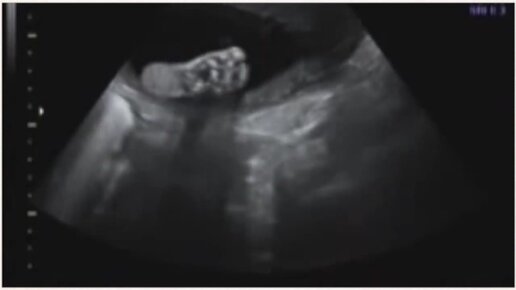

УЗИ на 28 неделе беременности